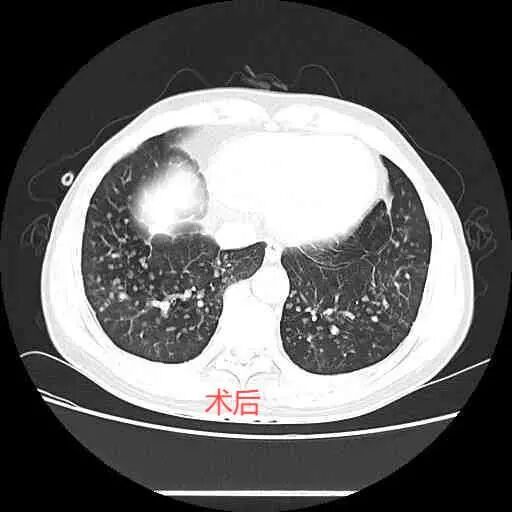

治療后,李剛術(shù)后第一天,水封瓶氣泡明顯減少,第二天水封瓶未見(jiàn)水柱波動(dòng),第三天復(fù)查,胸部CT提示氣胸明顯吸收,右肺逐漸恢復(fù)正常功能,隨后康復(fù)出院。